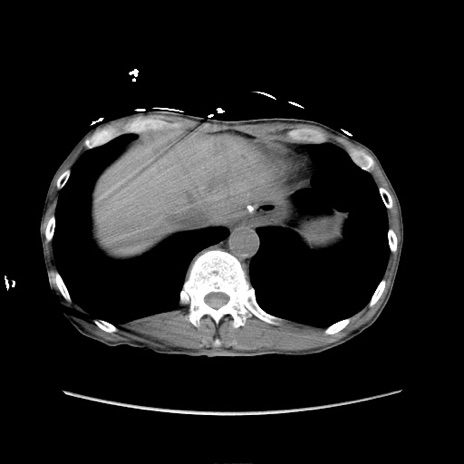

冠状断像